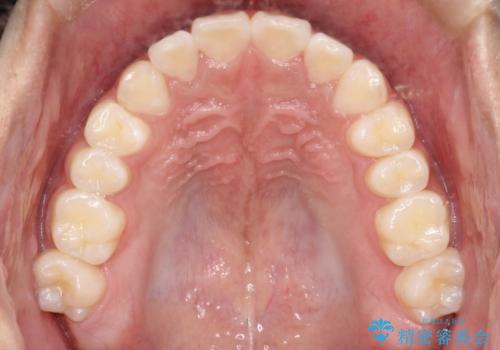

目立たずに矯正を終えることができ、患者様にも満足していただきました。